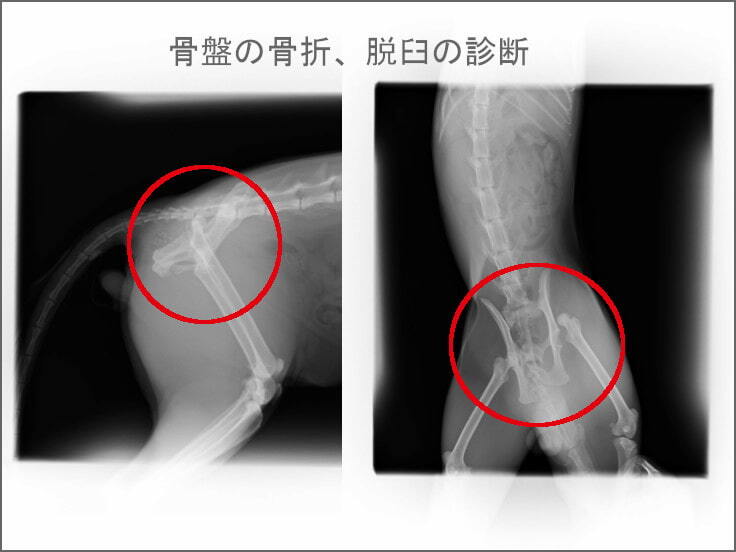

・骨盤骨折

・右股関節脱臼

骨折をしているので、内臓損傷の危険もあるとのこと。

骨盤の骨折、脱臼の手術のほか、去勢手術も一緒にしてもらいました。